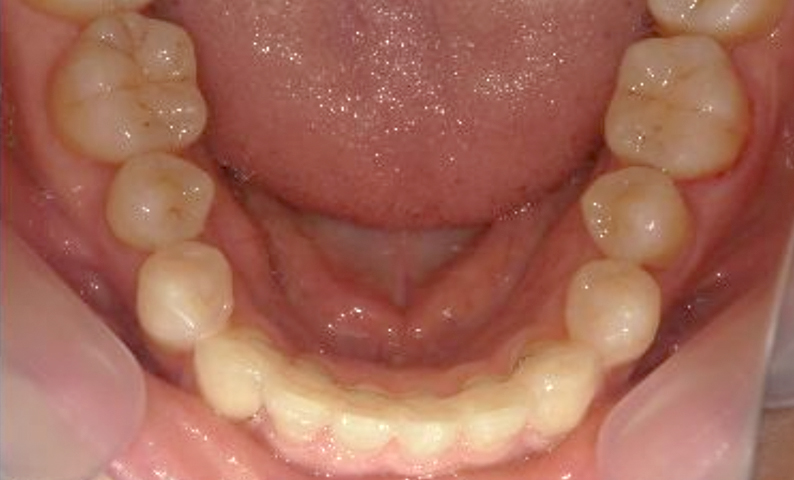

症例_003 上下顎の部分矯正

治療期間:12ヶ月金額:54万円+税男性八重歯前歯のガタガタ

| Before | After |